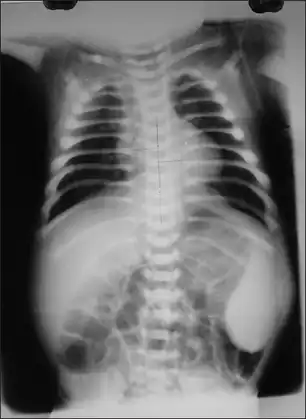

X-ray showing increased density in all the bones-Malignant infantile osteopetrosis -